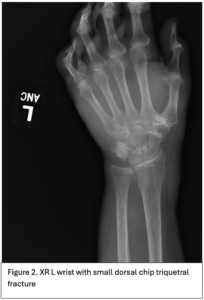

An 89-year-old right hand dominant female with dementia presented with significant swelling and bruising a left dorsal hand (Figure 1) after hitting the hand on a hand rail 10 days prior while being transferred to the bathroom at her nursing home. She has history of atrial fibrillation on Eliquis. Subsequently, the dorsum of her left-hand developed ecchymosis and became edematous. The patient was evaluated two days later at an out-patient facility where x-ray of the left hand showed no fractures or dislocations. The swelling and bruising continued to worsen and she was seen in the emergency department by the Plastic and Reconstructive Surgery team. A repeat 3V hand XR, 3V wrist XR, and CTA of the LUE were obtained, demonstrating a possible subtle dorsal chip avulsion from the triquetrum (Figure 2) and a dorsal hand hematoma (Figure 3 and 4) with a focal area of possible active extravasation (Figure 5) vs calcific density. She is a non-smoker.

Figure 1. Left dorsal hand demonstrating significant soft tissue edema extending to tips of the digits. Ecchymosis of left first and fifth digits, dorsum of hand and wrist, and distal posterior antebrachium. Blisters evident on dorsum of left hand and between second and third digits. Figure 2. X-ray of the dorsal left hand and wrist demonstrating minimally displaced triquetral fracture. A subtle fracture through the dorsal edge of the triquetrum could not be excluded. Figure 3. and Figure 4. Illustrate the burden of the hematoma. Figure 5. Appreciates a focus of enhancement suggesting bleeding or possible dystrophic calcification, however with clinical correlation it was determined more likely to be an active bleed